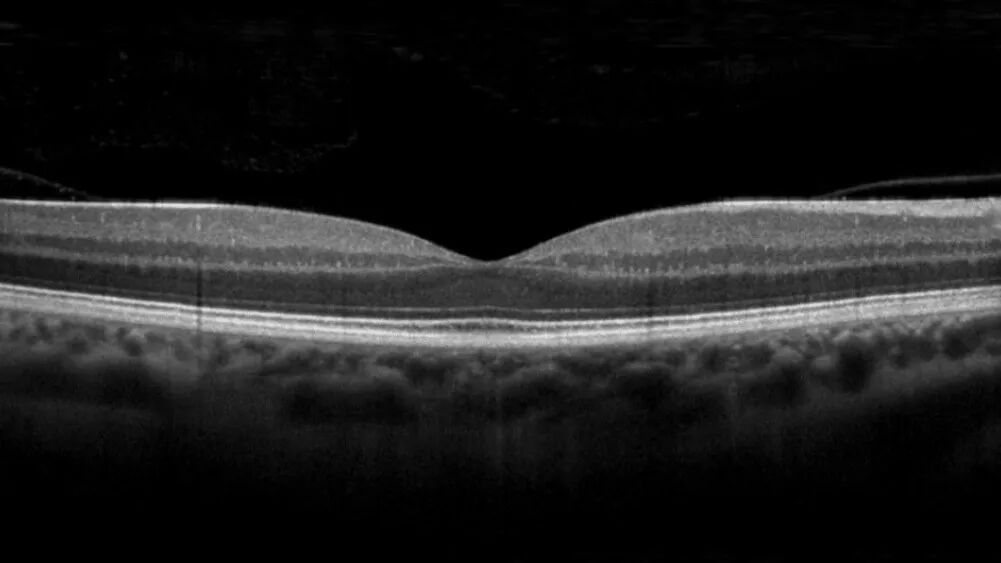

黄斑劈裂、黄斑裂孔